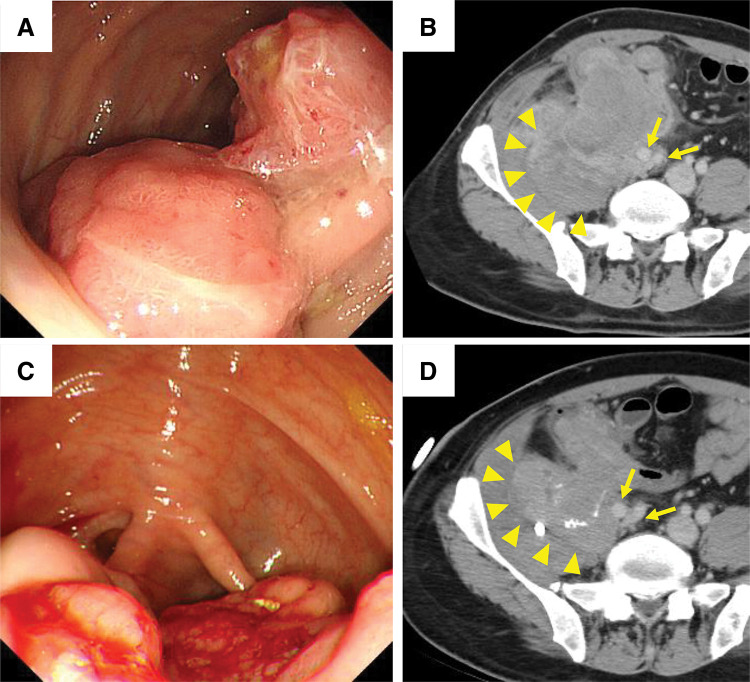

Case presentation: A 47-year-old male presented with advanced cecal cancer involving the right external iliac artery and vein, right femoral nerve, right ureter, right psoas muscle, and right iliacus muscle. He received systemic chemotherapy with a vascular endothelial growth factor inhibitor for 20 months, and percutaneous drainage of a psoas abscess was performed at a previous hospital. Following these interventions, he was referred to our hospital for radical resection. An F-F bypass was performed prior to abdominal surgery, and en bloc resection of the cecal cancer was subsequently achieved, encompassing the common iliac vessels, femoral nerve, iliacus muscle, psoas muscle, and ureter. The patient showed no signs of recurrence, graft infection, or occlusion 2 years postoperatively.